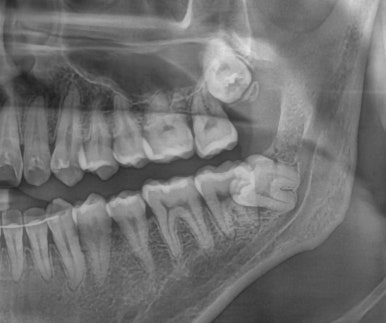

3. 사랑니에 충치가 생긴 경우

| 발치 전 구강사진 | 발치 전 엑스레이 | 발치 후 엑스레이 |

사랑니 위치는 수복 치료가 어렵고,

옆 치아까지 영향을 줄 수 있어 조기 발치를 권합니다.